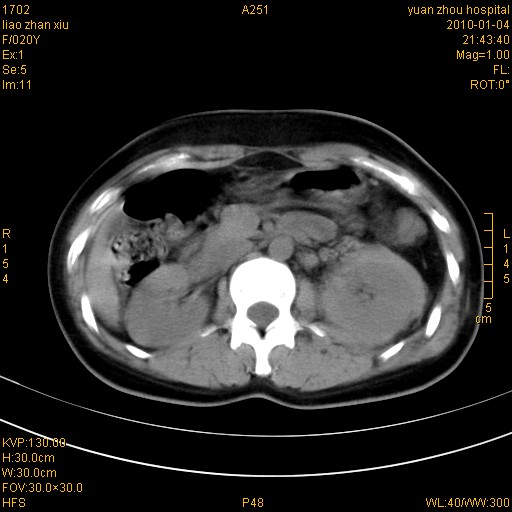

标题: CT23985:F20Y 外伤典型病例

左肾挫伤,包膜下积血。

左肾挫裂伤伴肾被膜下积血!另:肾周筋膜增厚!

1)左肾包膜下血肿。2)左侧肾挫伤可能;建议:行ct增强扫描检查。3)腰椎左侧横突骨折。

左肾挫伤,包膜下积血,l3、4左侧横突多发骨折。

双侧肾胞膜下出血,左侧较多。l3、4左侧横突多发骨折。

1、左肾挫伤,包膜下积血;

2、l3、4左侧横突多发骨折;

3、腹腔积气,考虑肠管破裂?

左肾挫伤,包膜下积血,L1、2、3、4左侧横突多发骨折。